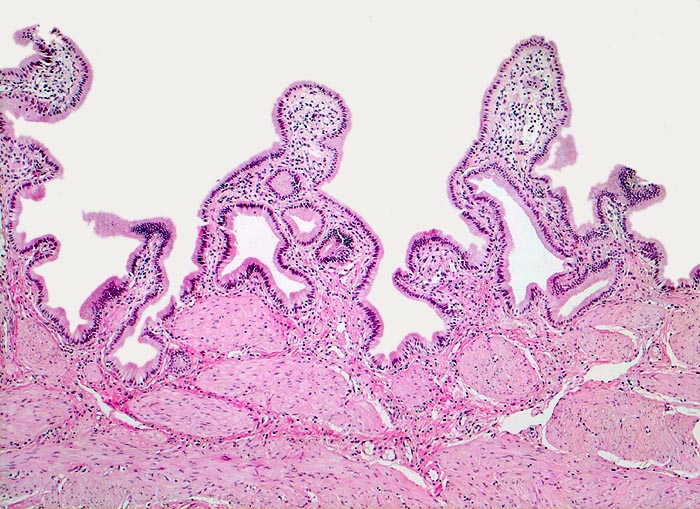

AP/ Chronische Cholezystitis

Chronische Cholezystitis

Gallenblase